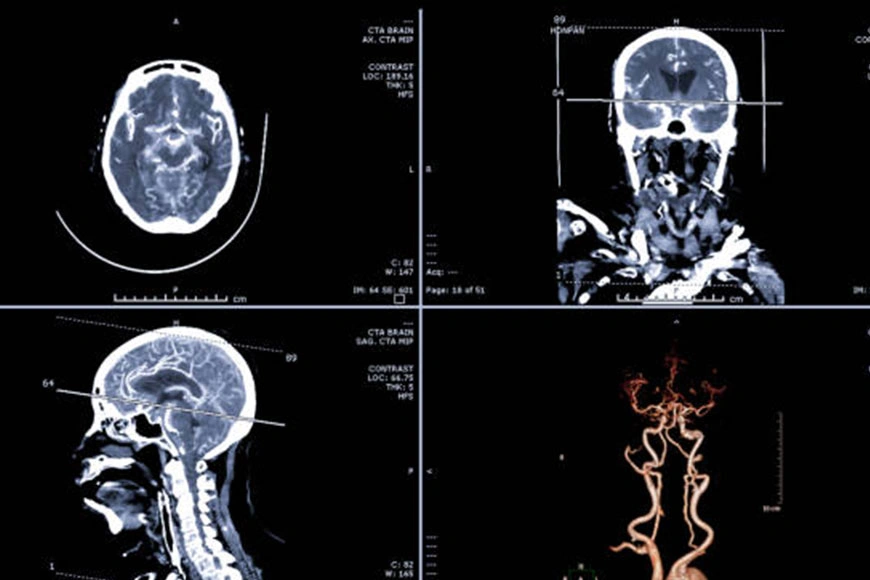

Angio Brain/Neck is a medical imaging test that uses advanced technology to visualize the blood vessels in the brain and neck. This non-invasive diagnostic test is used to diagnose various medical conditions such as stroke, aneurysm, and arteriovenous malformations (AVMs) that affect the blood vessels in the brain or neck.

The test is usually performed using a CT or MRI machine, which uses a powerful magnetic field and radio waves to create detailed images of the blood vessels in the brain and neck. During the test, the patient will lie down on a table that slides into the machine. The machine will then take multiple images of the brain and neck, which will be analyzed by a radiologist or a neurologist.

The test usually takes between 30 minutes to an hour to complete, depending on the type of imaging technology used and the complexity of the case. After the test, the images will be analyzed by a radiologist or a neurologist, who will interpret the results and provide a report to the referring physician.

The results of the Angio Brain/Neck test are interpreted by a radiologist or a neurologist. The images may show abnormalities in the blood vessels, such as narrowing, blockages, or bulging, that may indicate a medical condition, such as an aneurysm or stroke. Depending on the severity of the findings, the healthcare provider may recommend further testing or treatment, such as medication, surgery, or lifestyle changes.